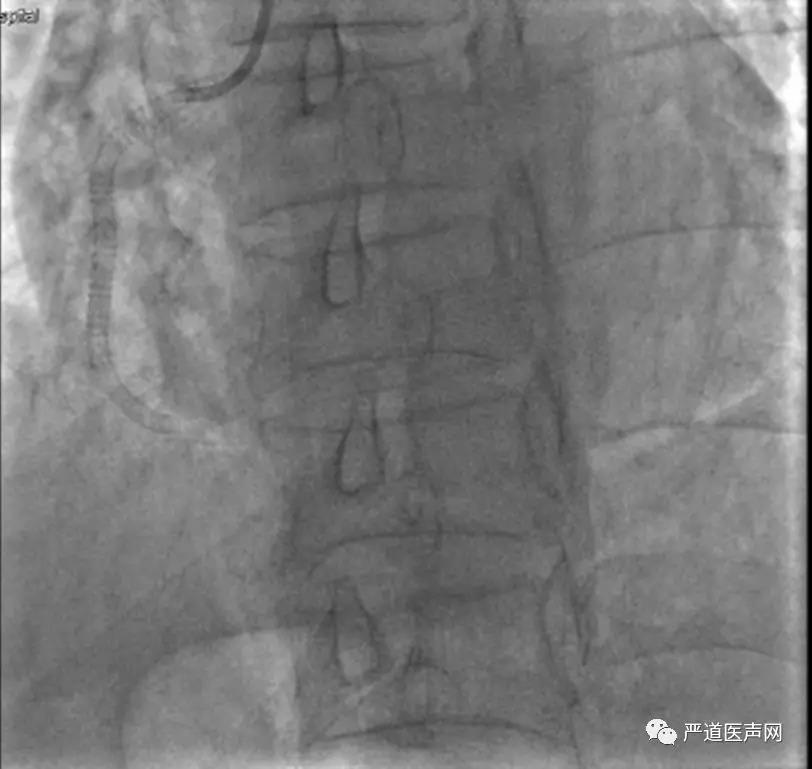

来自郴州市第一人民医院心血管病医院的王仲华主任为大家带来了一例右冠开口支架内CTO的精彩汇报。患者为55岁男性,2016年12月因“急性广泛前壁心肌梗死”于前降支近中段植入支架2枚,2017年2月在右冠近中段植入支架2枚。行双侧造影示:LAD支架畅通,与RCA形成侧支循环,RCA开口闭塞。由于RCA入口位置不定,指引导管无法判断是否到达入口,无法定位原支架的位置,而LAD有侧支循环,决定选择逆向途径。

手术策略为正向微导管等待逆向微导管及导丝。术中逆向入Sion导丝,Corsair 150mm微导管跟进困难,故更换Finecross 150mm微导管后顺利通过,逆向导丝升级入前向指引导管,但逆向微导管跟进困难,遂正向指引导管再入Corsair150mm微导管Rendexous成功。

前向Corsair微导管无法通过RCA C1段。原因可能为前向Guiding支持不足、支架内闭塞组织坚韧、原有病变钙化+支架膨胀不全、导丝行走于支架外等。遂后退逆向导丝、微导管,前向通过Sion导丝,但前向Corsair微导管仍然无法通过,退出,使用1.2mm球囊后扩张,最终植入两枚Excel(爱克塞尔)支架。